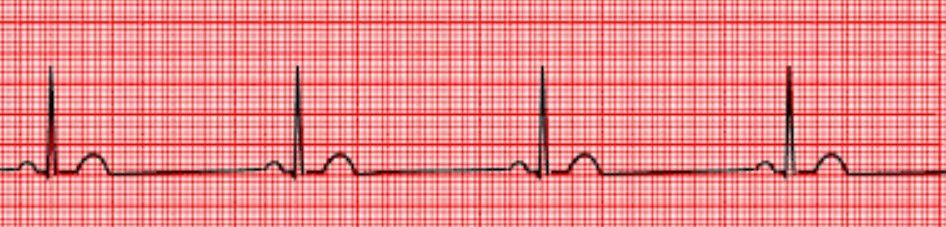

- Q1Identify.Atrial FibrillationVentricular TachycardiaNormal Sinus RhythmVentricular Fibrillation30s

- Q2Identify.Atrial FlutterNormal Sinus RhythmVentricular FibrillationAtrial Fibrillation30s

- Q3Identify.Normal Sinus RhythmAtrial FlutterAtrial FibrillationVentricular Fibrillation30s

- Q4Identify.Premature Ventricular ContractionAtrial FibrillationVentricular FibrillationPremature Atrial Contraction30s

- Q5Identify.Ventricular FibrillationPremature Ventricular ContractionPremature Atrial ContractionAtrial Fibrillation30s

- Q6Identify.Normal Sinus RhythmSinus BradycardiaVentricular TachycardiaSinus Arrhythmia30s

- Q7Identify.Sinus TachycardiaNormal Sinus RhythmSinus BradycardiaSinus Arrhythmia30s

- Q8Identify.Normal Sinus RhythmSinus TachycardiaSinus BradycardiaAtrial Flutter30s

- Q9Identify.Normal Sinus RhythmVentricular TachycardiaAtrial FibrillationVentricular Fibrillation30s

- Q10Identify.Sinus BradycardiaVentricular TachycardiaNormal Sinus RhythmAtrial Flutter30s